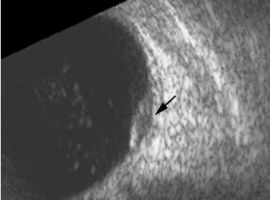

B- and A-scans provide important clinical information about the lesions both for identification and for exclusion of differentials. Ultrasonographic form and internal features should be noted.

Ultrasonographic Form

In the case series of 56 eyes with PEHCR by Mantel et al.[7], about half of the lesions were dome-shaped and the other half multi-lobar on the B scan. "Plateau-shaped elevation lesions" were described by Shields et al[5], and the term may describe lesions lesions with a large base diameter. Highly irregular lesions were also observed in a small minority (3.6%) of the patients per Mantel et al although in none of the eyes reviewed by Shields et al.

The average thickness of the lesions is between 2mm and 3mm in the series by Mantel et al and Shields et al, ranging from 1.0 to 9.0mm. The basal dimension ranged from 10mm to 25mm with average of 10.1mm in the series by Shields et al[5] with no evidence of choroidal excavation. This is a subtle diagnostic feature that separates PEHCR from choroidal melanoma.

Serial measurement of the basal diameter and elevation of the lesion is useful in confirming regression or stability of the lesion.

Ultrasonographic Features

The features of the lesions range between hollow, solid, intermediate, and irregular in acoustic quality, which may correspond to the clinical and/or angiographic evidence of hemorrhagic PED vs. serous pigment epithelium detachment. Shields et al[5] commented that 100% of the eyes in their series of 173 eyes lacked intrinsic vascular pulsation, which is important in differentiating the lesion from choroidal melanoma. Another distinguishing feature of PEHCR is the presence of clot "retraction cleft" that separates the sub-retinal or sub-RPE clot from the underlying choroid visible on ultrasonography. Retraction cleft is not seen with melanomas.

Internal Reflectivity

There is no classic feature of PEHCR on A-scan. Of the 130 eyes that had A-scan data from the series by Shields et al[5]., internal reflectivity of the lesions ranged between low, intermediate, and high (41%, 36, and 19% respectively) depending on the chronicity and density of hemorrhage. Note that melanomas classically have low to medium internal reflectivity on A-scan[1].